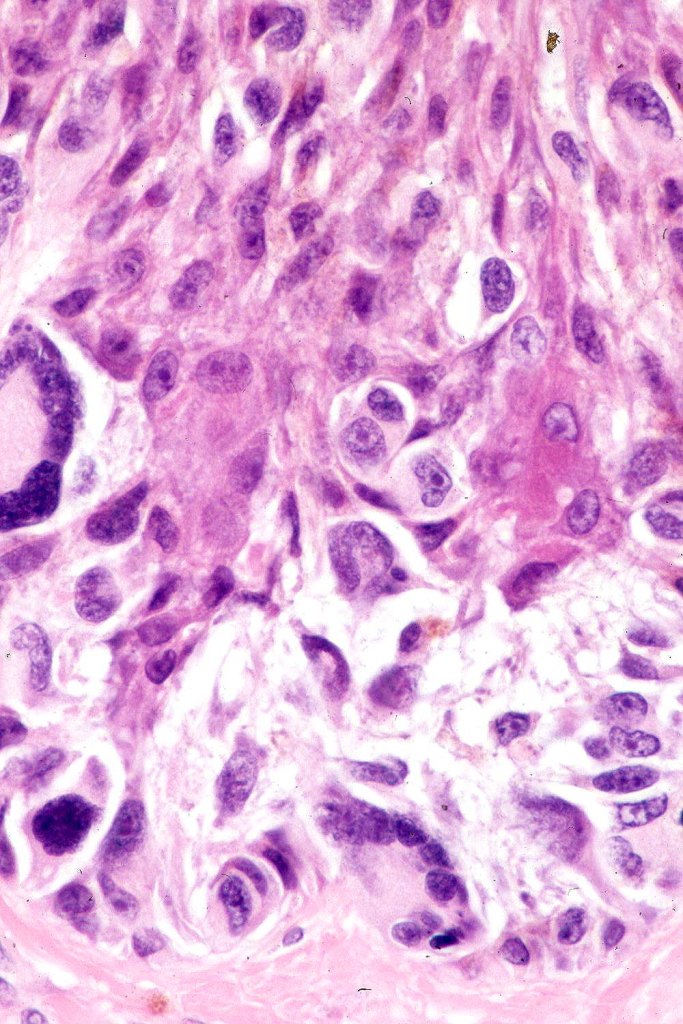

•Cytoplasmic retraction artifact, nuclear hyperchromatism with irregular borders

•Multinucleate giant cells

•Mitoses can be conspicuous

•Pagetoid spread

•Invasive tumor (lentigo maligna melanoma) typically characterized by a spindle cell population